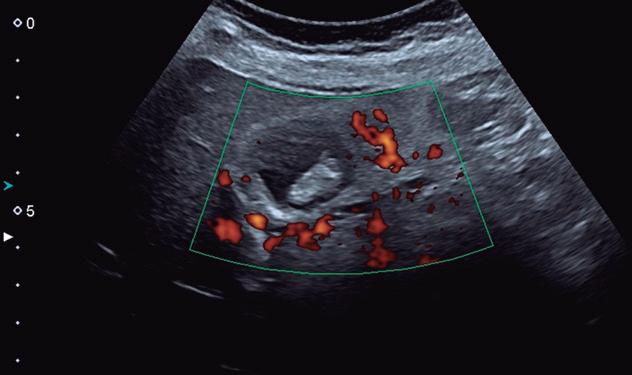

Fig. 2-65. Colecistite – Doppler mostrando hipervascularização das paredes da vesícula.